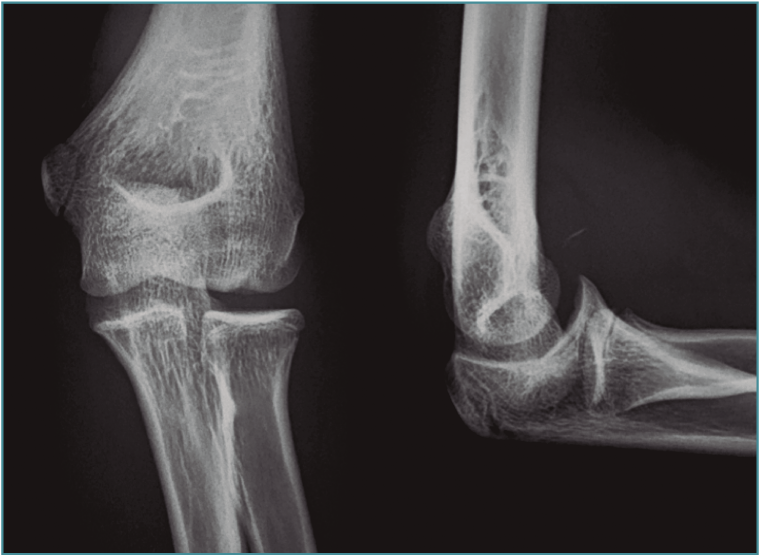

El diagnóstico de imagen se realiza mediante radiografías en 4 proyecciones (anteroposterior, lateral y oblicuas a 45°), apreciándose esclerosis del capitellum, líneas de radiolucencia y cuerpos libres (Figura 1). No obstante, tiene una utilidad muy limitada. Kijowski y De Smet(7) demostraron que menos del 50% de las ODC en estadios iniciales pueden ser diagnosticadas por estudios radiológicos con proyecciones simples. Además, estas proyecciones no permiten identificar la presencia de cuerpos libres en el mayoría de los pacientes.

Figura 1. Imagen radiológica de una lesión osteocondral en el capitellum de una gimnasta de 15 años de edad.